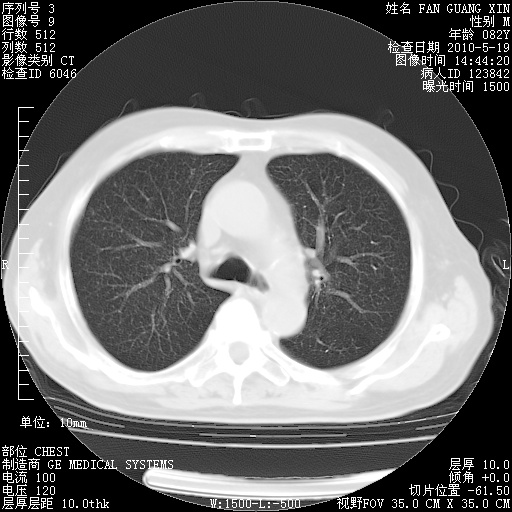

复查肺部CT,明显好转。为什么发热呢?

治疗3周后的肺部CT

治疗3周后的肺部CT纵隔窗